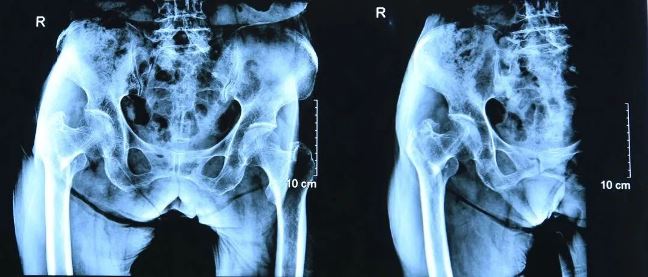

術(shù)前影像

患者黃阿姨,93歲,在家中行走時(shí)不慎摔倒,導(dǎo)致右股骨粗隆間骨折。當(dāng)即感覺(jué)右髖關(guān)節(jié)劇烈疼痛,右下肢功能活動(dòng)受限,不能站立行走。家屬經(jīng)過(guò)多方打聽(tīng),對(duì)宏大醫(yī)院副院長(zhǎng)、骨科主任喬建民教授在骨科方面的手術(shù)技術(shù)十分認(rèn)可,從鶴崗市綏濱縣慕名而來(lái),4月18號(hào)入住我院,喬院長(zhǎng)組織骨科醫(yī)療組立即為患者完善各項(xiàng)檢查,經(jīng)反復(fù)詳細(xì)的術(shù)前討論及綜合評(píng)估,為其制定了個(gè)體化的手術(shù)方案。

據(jù)喬建民院長(zhǎng)介紹:“股骨粗隆間骨折是老年患者常見(jiàn)的骨折類型之一。老年患者骨質(zhì)疏松嚴(yán)重,其中發(fā)病率女性較高。生活中不慎跌傷及車禍傷均可致股骨粗隆間骨折。傷后髖部腫脹、疼痛、肢體屈曲短縮外旋畸形,再行相關(guān)影像學(xué)檢查,即可明確診斷。老年人骨折臥床后,極易發(fā)生各種并發(fā)癥,如墜積性肺炎、壓瘡、下肢深靜脈血栓形成、泌尿系感染等,如處理不當(dāng),將嚴(yán)重影響治療效果,甚至造成災(zāi)難性的后果。手術(shù)需盡早進(jìn)行。